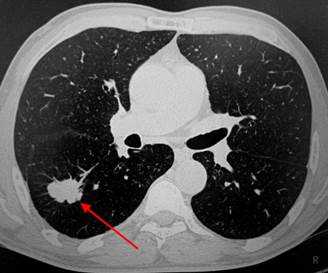

Слева - рак почки с метастазами в легкие, прогноз в данном случае неблагоприятный ввиду метастатического плеврита и дыхательной недостаточности. Определяются очаги с обеих сторон. Справа - мелко- и среднеочаговая диссеминация при раке печени.

Множественные гематогенные вторичные узлы при раке почки, компьютерная томография (КТ).